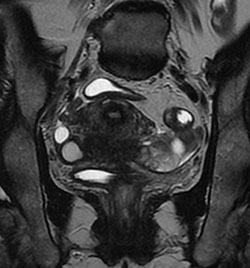

O curso foca em uma abordagem prática e atualizada da ressonância magnética da PELVE FEMININA, com base nos principais consensos de ENDOMETRIOSE e metodologia de APRENDIZADO BASEADO EM CASOS RADIOLÓGICOS (ABC-RAD).

Em cada encontro será abordado um tema dentro do assunto ENDOMETRIOSE, com discussão dos casos selecionados e EXPLICAÇÃO DAS IMAGENS, com acesso ao LAUDO DETALHADO no final de cada caso.